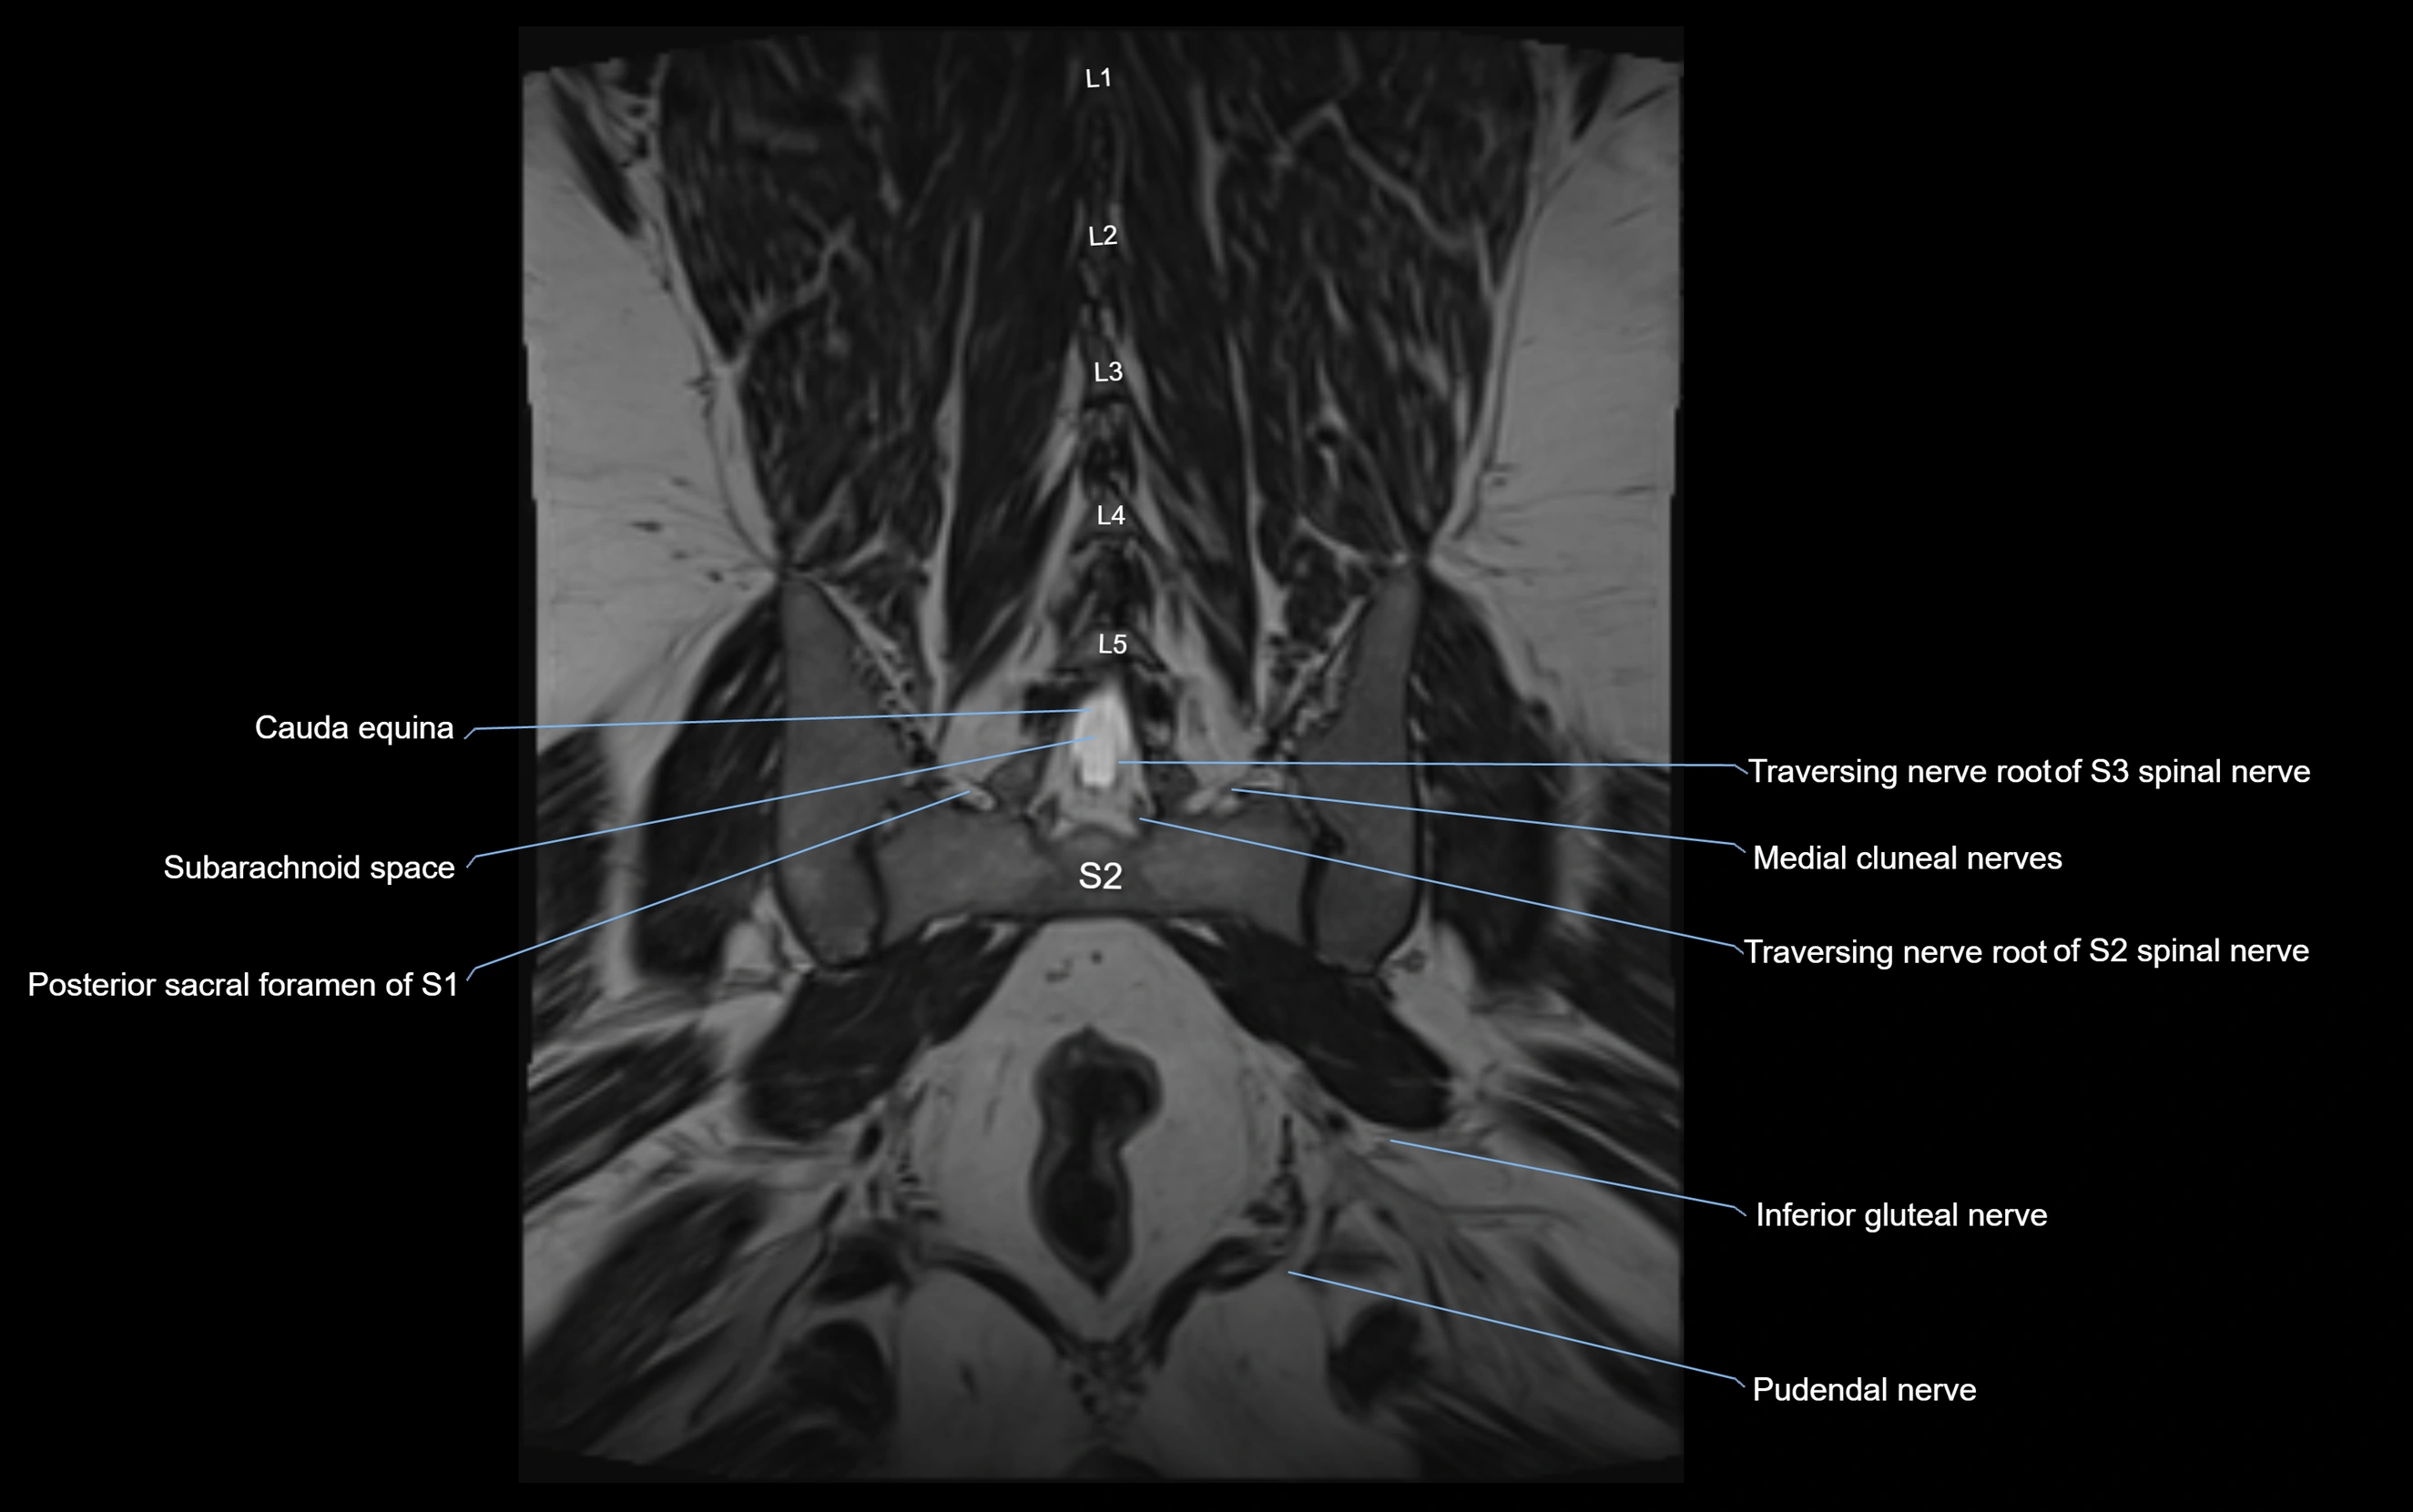

MRI image

image